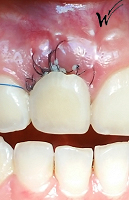

Après la guérison des tissus mous (gencive) et durs (os alvéolaire), la couronne céramique esthétique a été installée sur l’implant.

Le maintien de l’esthétique du sourire dépend en grande partie de la reconstruction des tissus gingivaux entourant la couronne céramique esthétique et de l’os autour de l’implant.